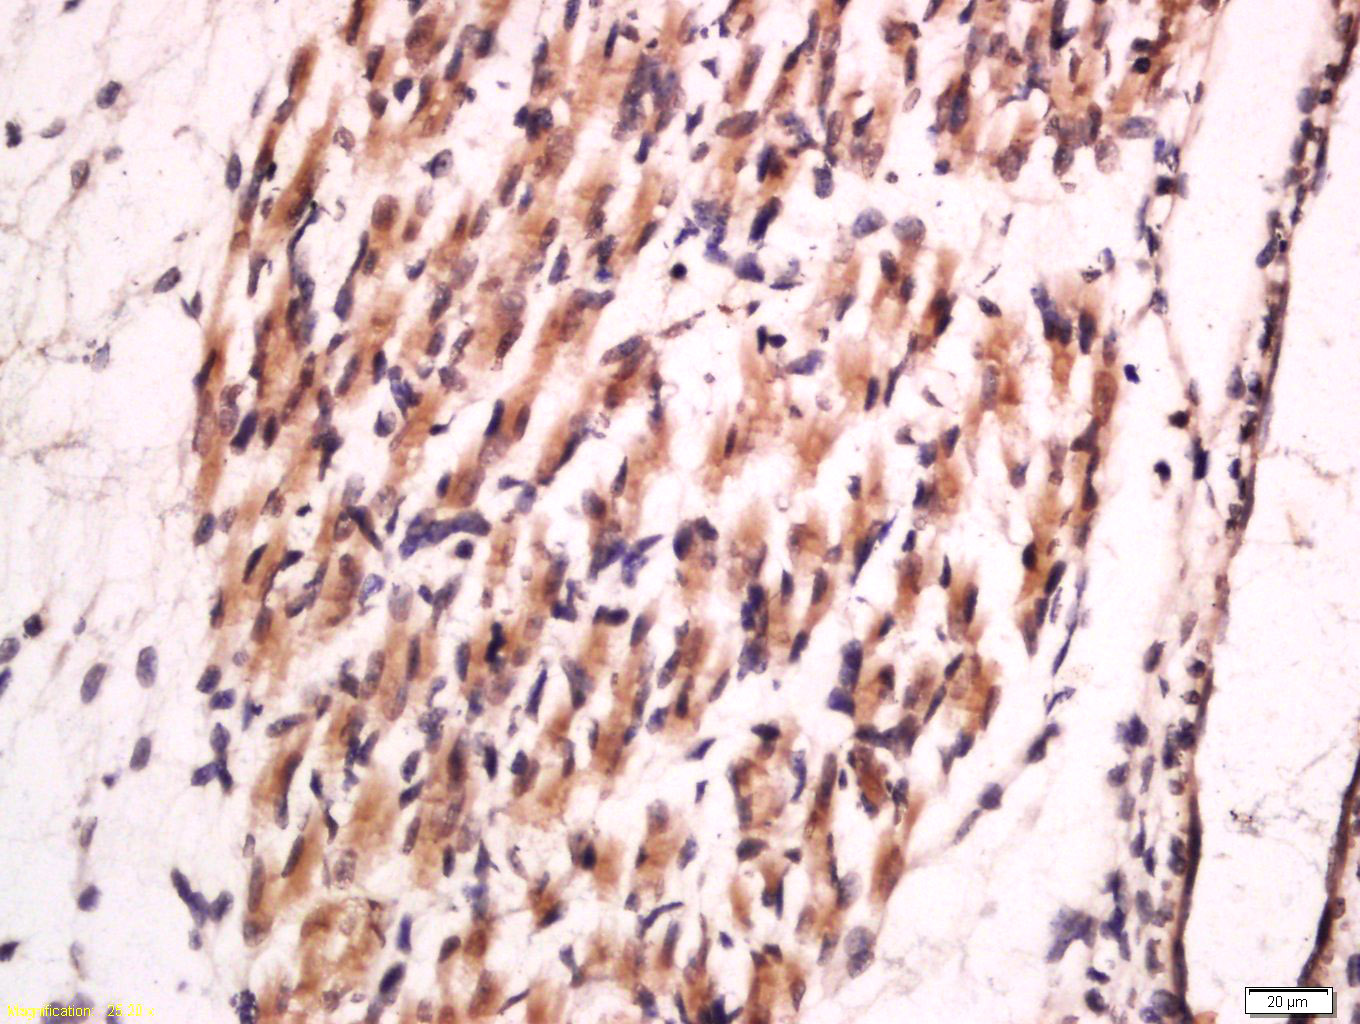

Tissue/cell: Mouse embryo tissue; 4% Paraformaldehyde-fixed and paraffin-embedded; Antigen retrieval: citrate buffer ( 0.01M, pH 6.0 ), Boiling bathing for 15min; Block endogenous peroxidase by 3% Hydrogen peroxide for 30min; Blocking buffer (normal goat serum,C-0005) at 37∩ for 20 min; Incubation: Anti-Collagen II Polyclonal Antibody, Unconjugated(bs-10589R) 1:100, overnight at 4∑C, followed by conjugation to the secondary antibody(SP-0023) and DAB(C-0010) staining